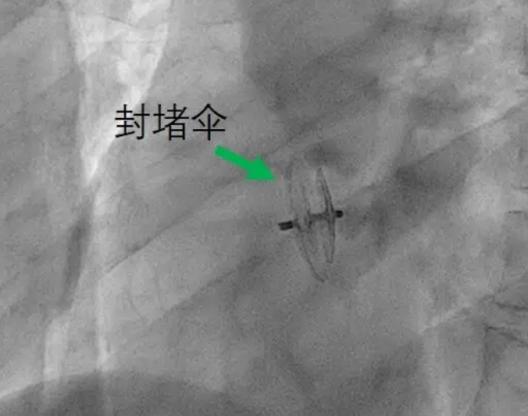

3月29日,我院结构性心脏病诊疗中心介入治疗单元专家团队在东院区介入导管室,为患者成功实施了“卵圆孔封堵术”。局麻下穿刺股静脉,经过未闭卵圆孔建立轨道,将封堵器送达卵圆孔部位嵌入“小孔”阻断异常血液分流,最后由超声进一步检查确认封堵效果,用时不到一小时。